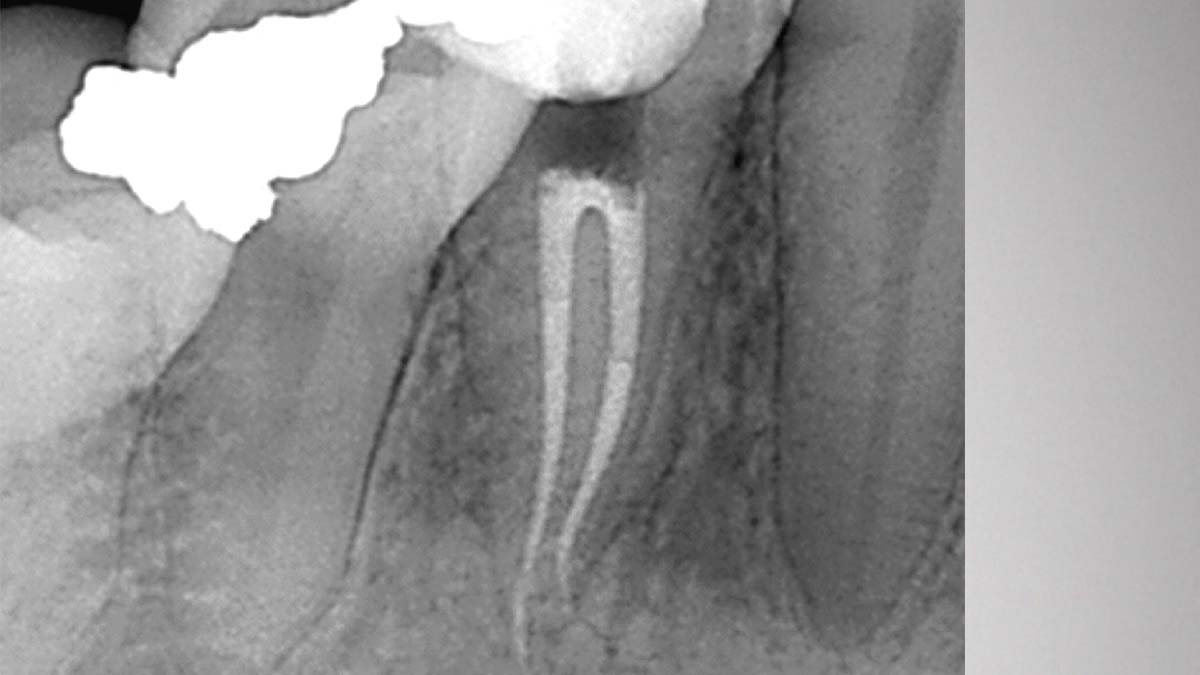

Rechts: Gutta-Smart und Conform Fit bieten die gleiche moderne Guttapercha für radiographische Konsistenz.

Bild mit freundlicher Genehmigung von Dr. Nathaniel Behrents, Fayetteville, AR